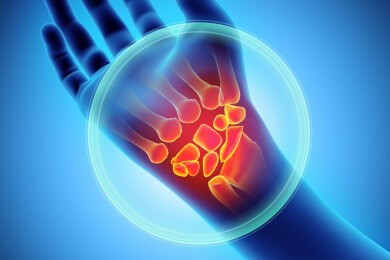

- Knochenbruch im Handgelenk: Unkomplizierte Brüche im Kahnbein müssen selten operiert werden

Wer sich die Hand bricht, muss nicht nur viele Wochen mit Gips und daher großen Bewegungseinschränkungen rechnen, im schlimmsten Fall steht ...

- Karpaltunnelsyndrom & Co: Schmerzen in der Hand näher erklärt

Wenn die Hand Schmerzen bereitet, hat der Mensch ein Problem, denn die Hände werden täglich zur Ausführung unterschiedlichster Tätigkeiten ...

- Schmerzen in der Hand: Welche Ursachen sind am häufigsten?

Besonders in Berufen mit viel Schreibtischarbeit sind Schmerzen in der Hand verbreitet. Doch auch unter Sportlern und in Jobs mit sich häufig ...